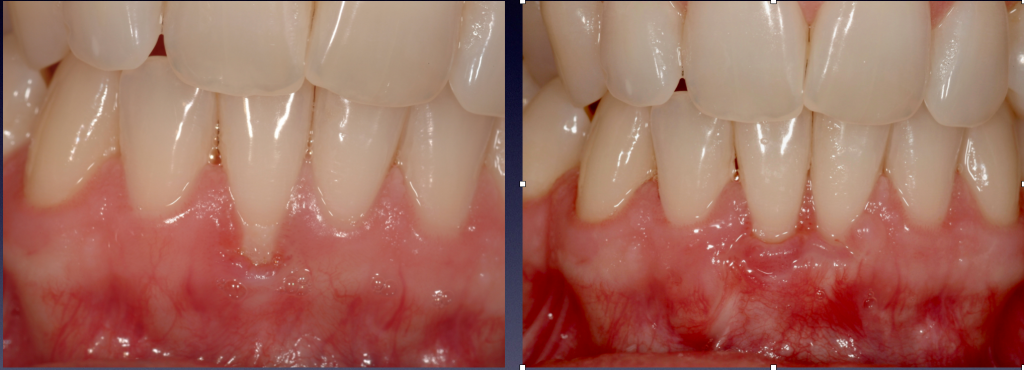

Recession around incisors

Following procedure to cover gingival recession